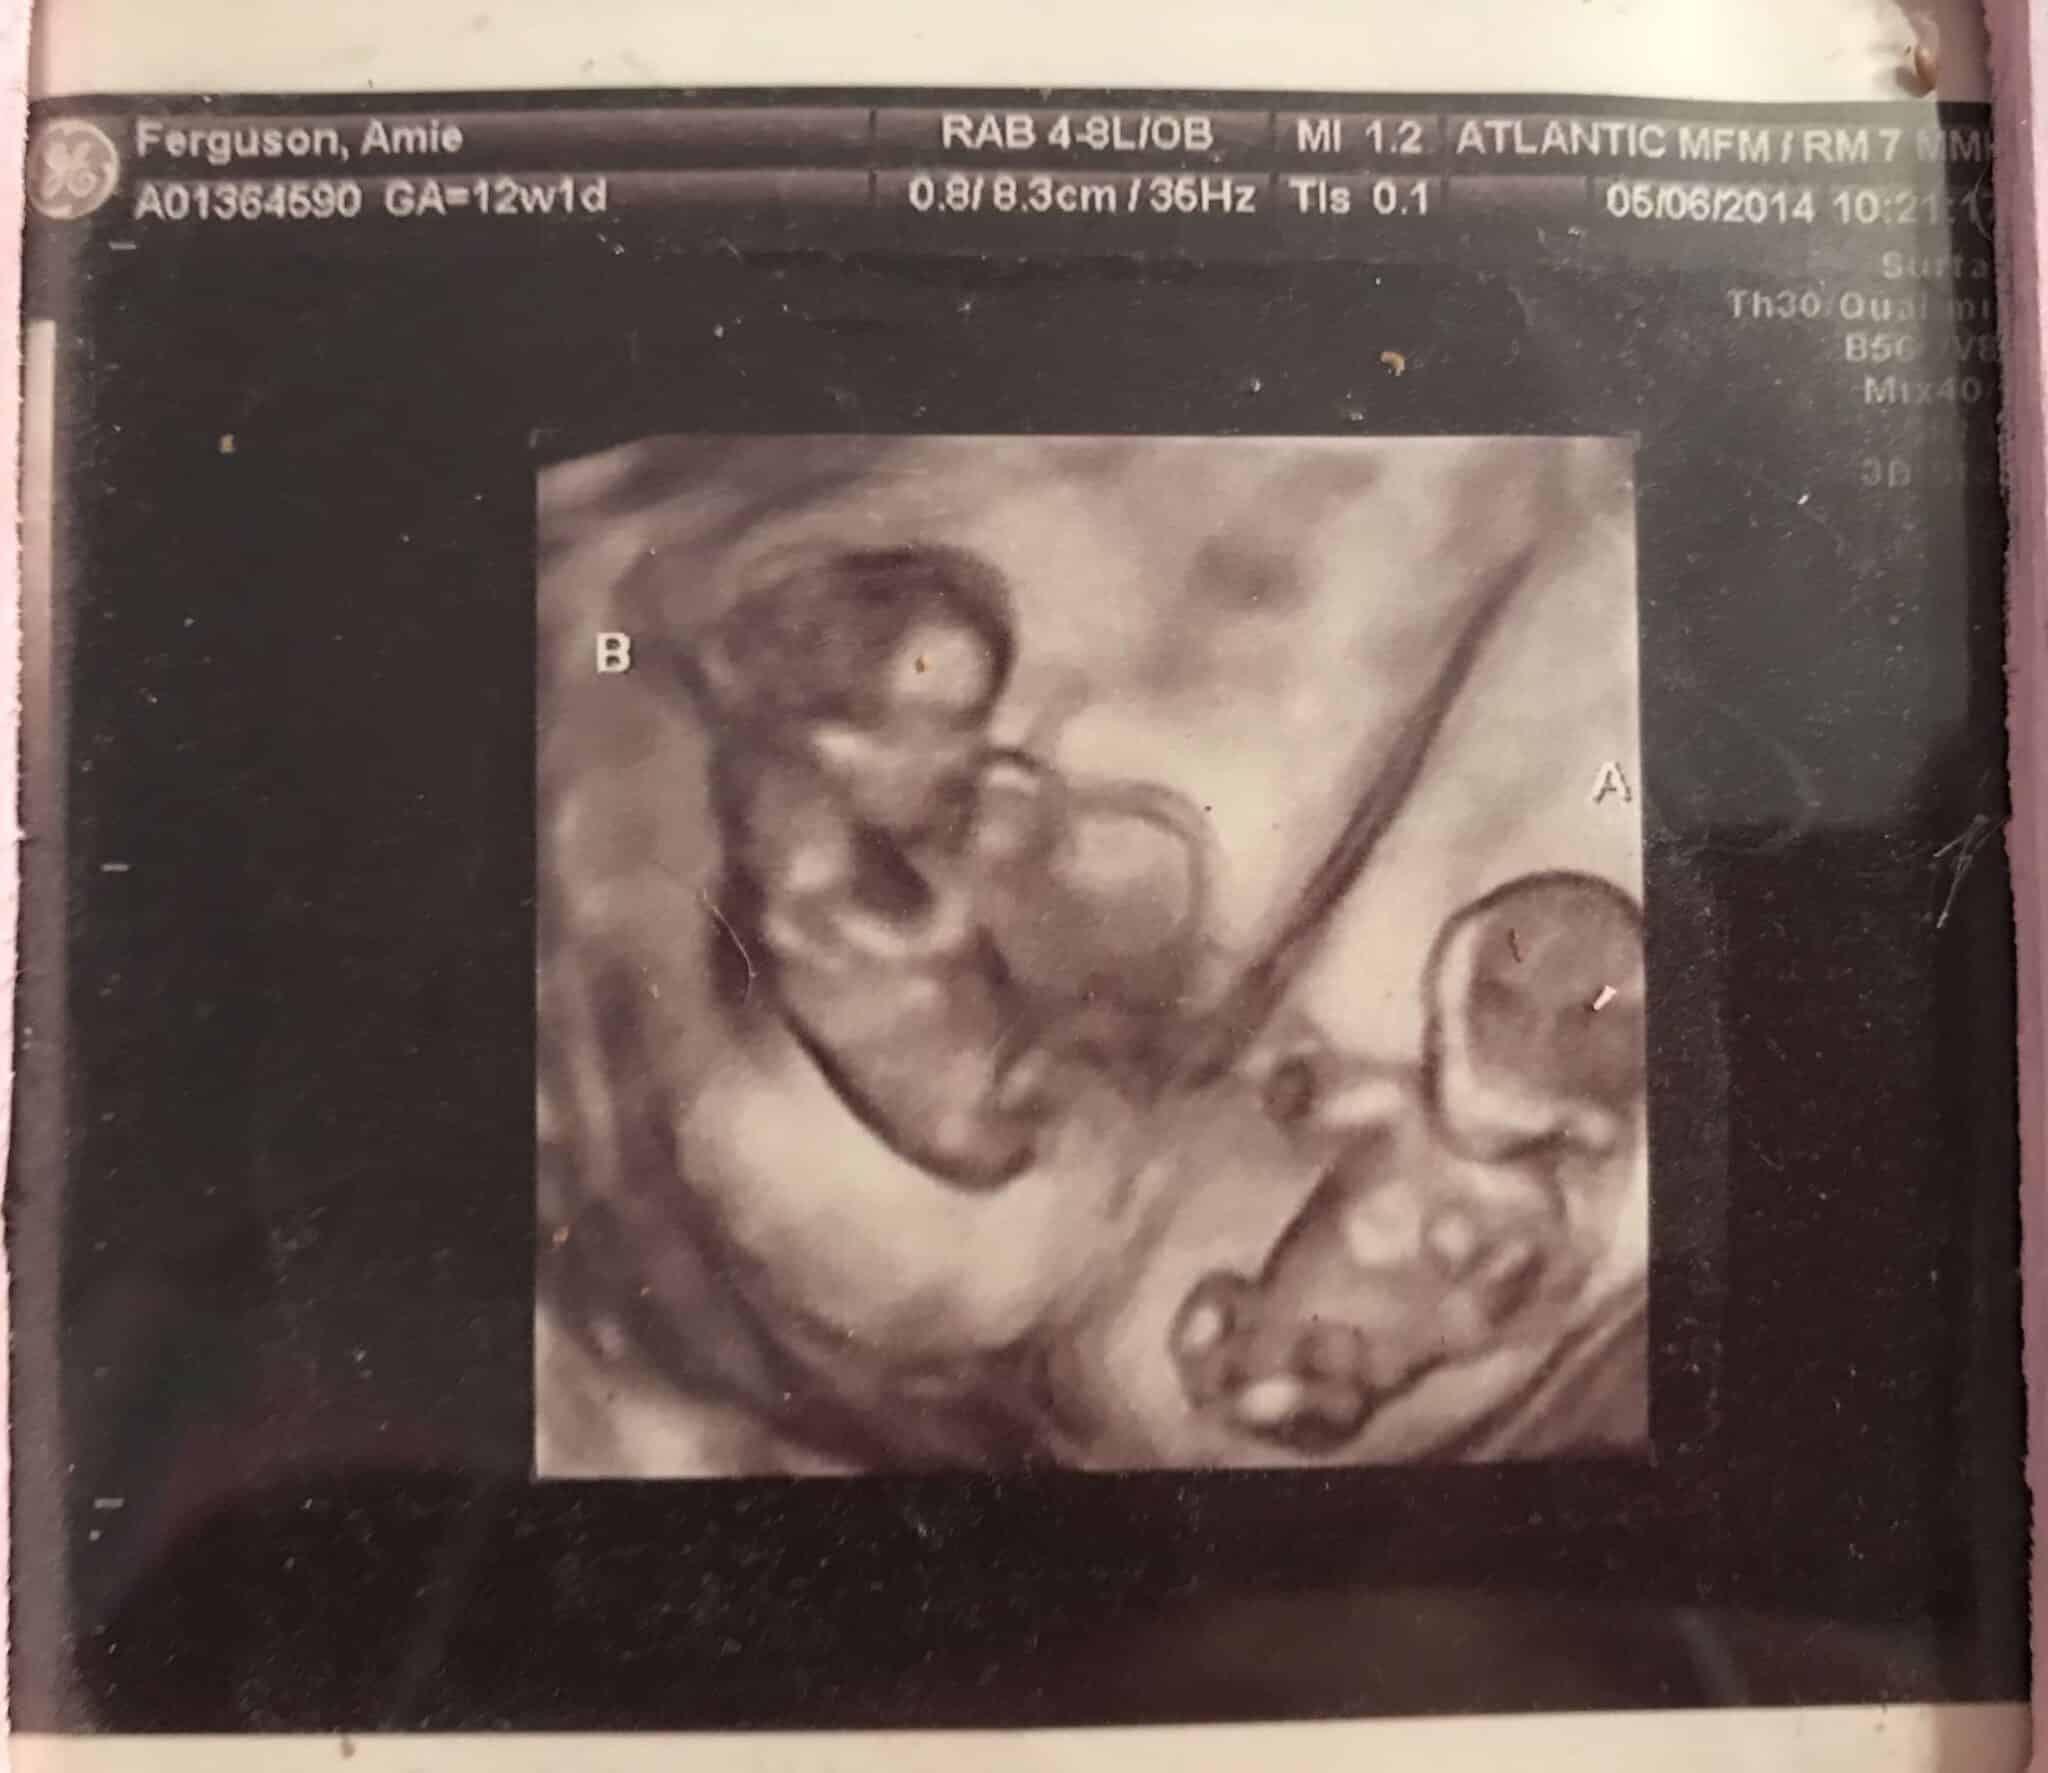

Ultrasound Photos at 12 Weeks Pregnant With Twins